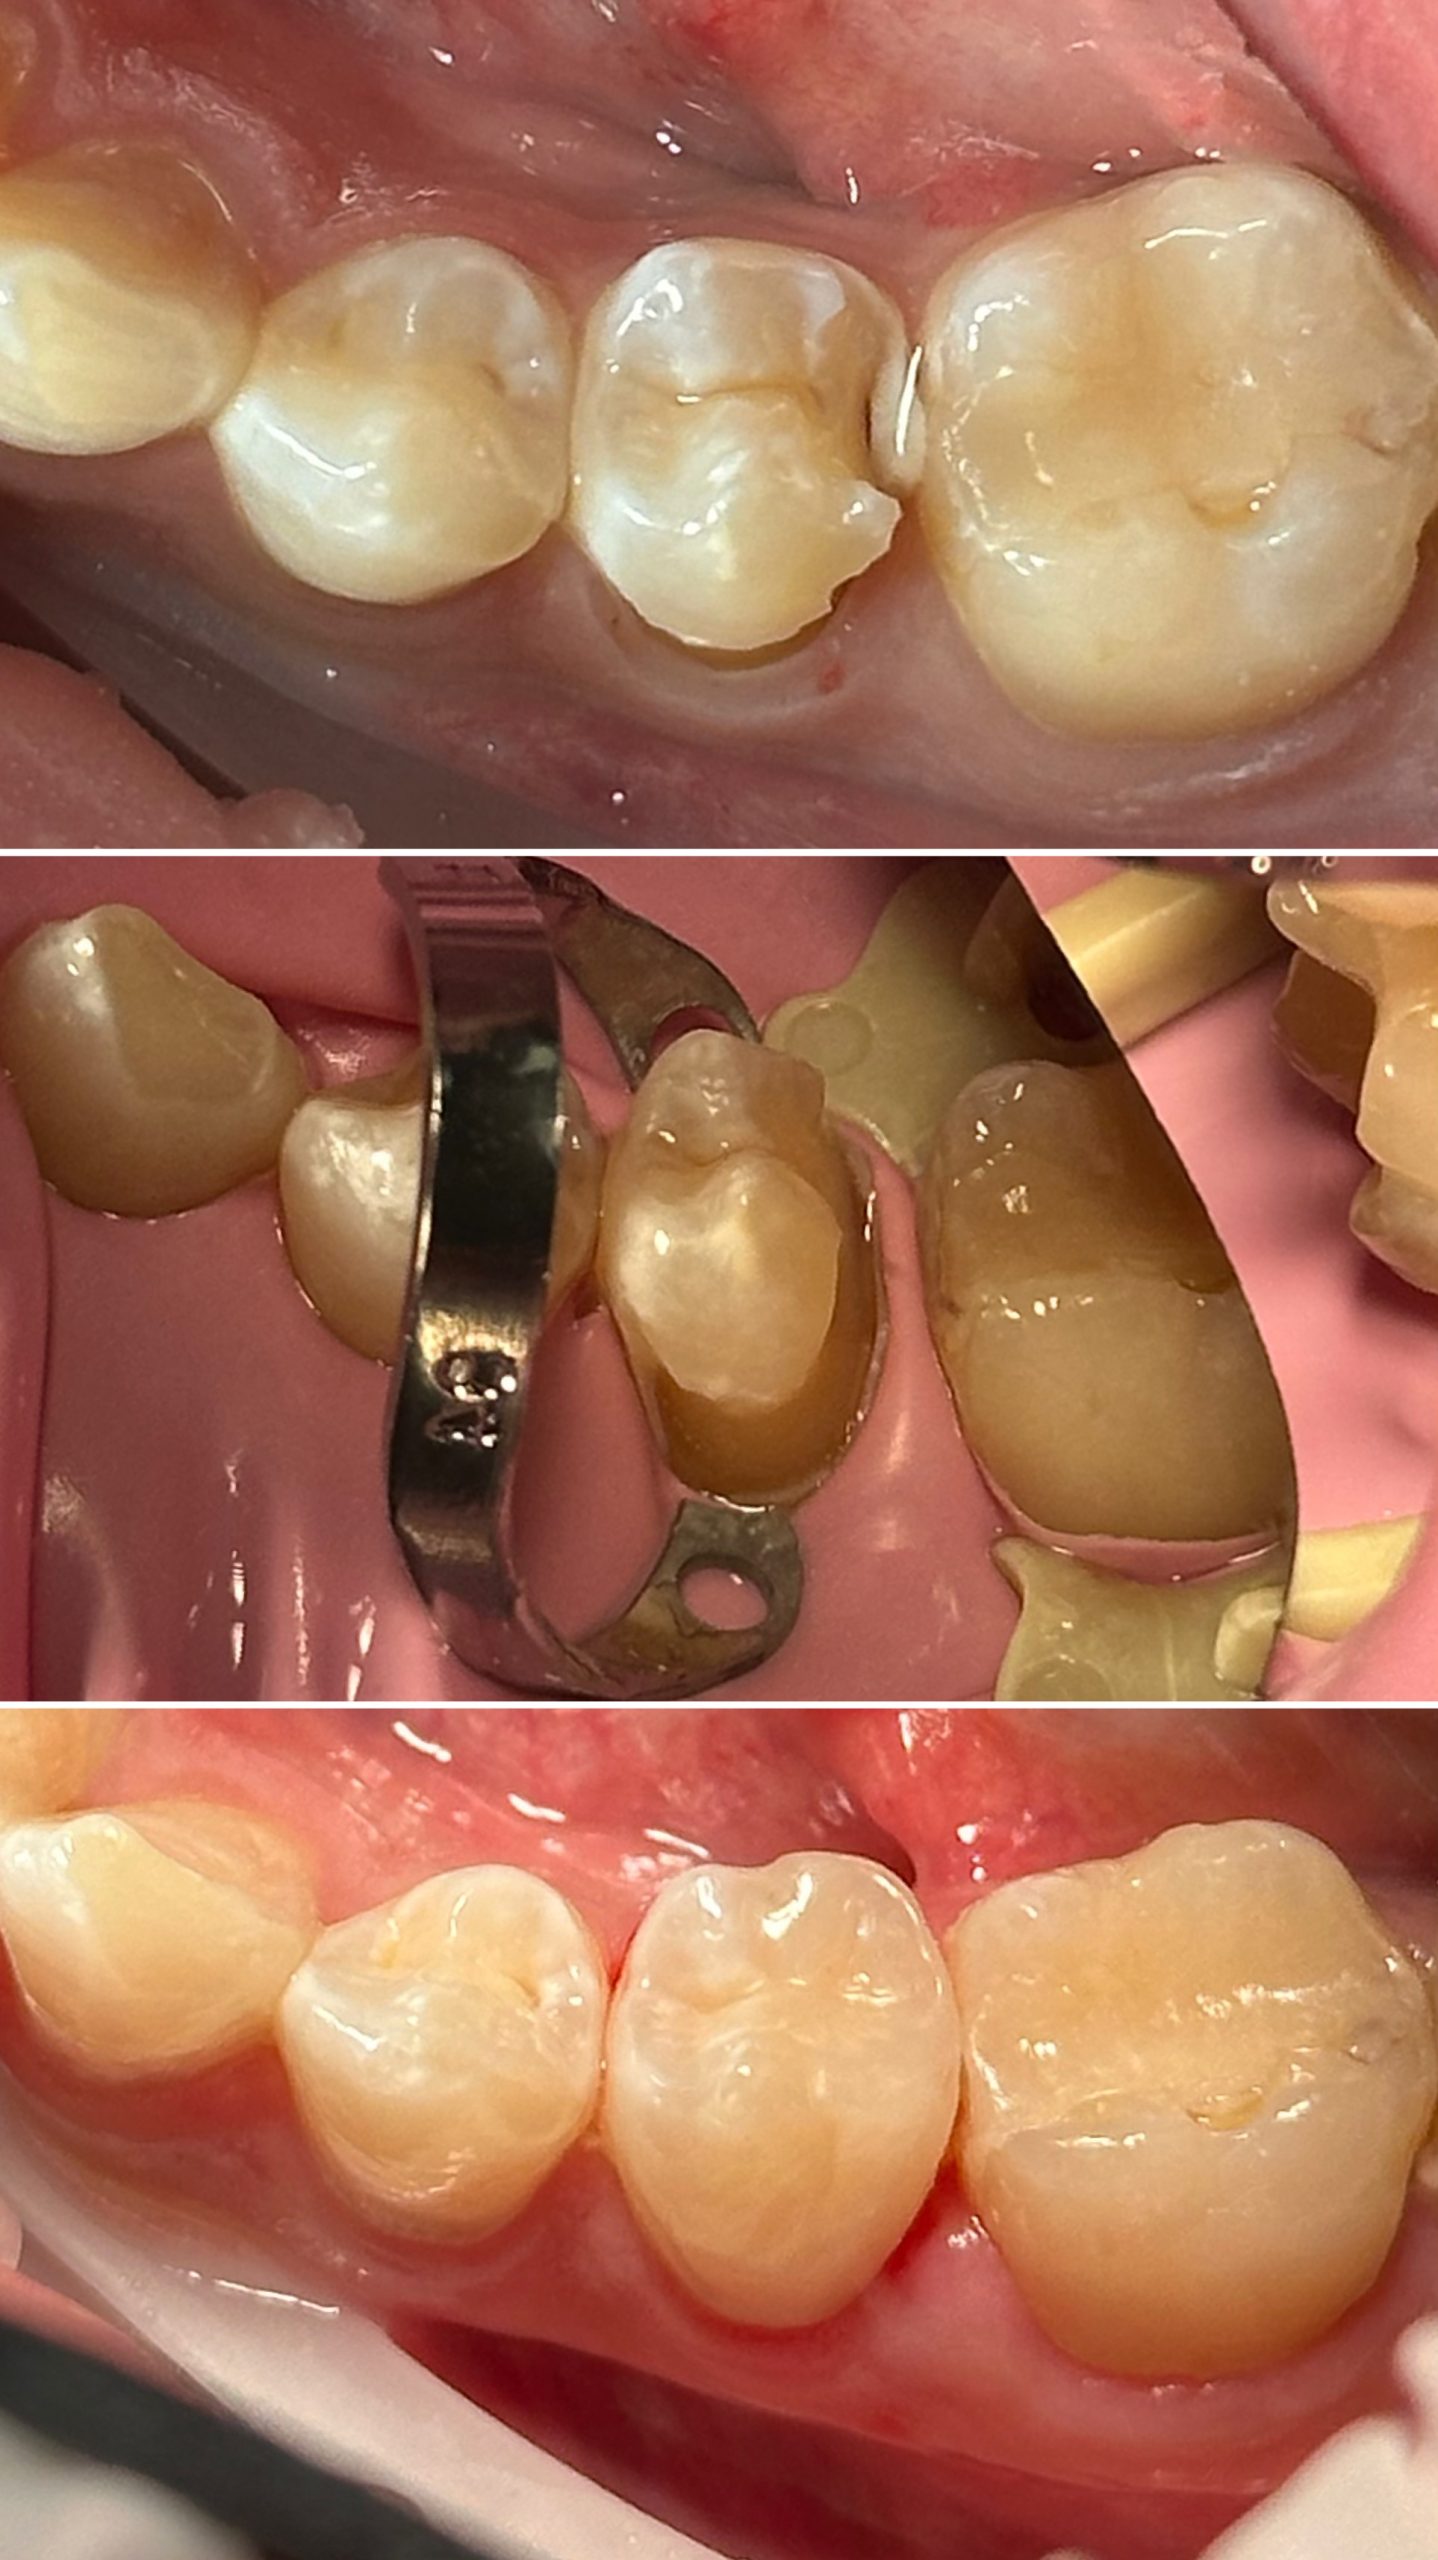

• Диагностика и лечение кариеса и его осложнений (пульпиты, периодонтиты)

• Художественная реставрация фронтального и бокового участка зубов

2021 год – «Применение кофердама в стоматологической практике» учебный центр «Fenestra»